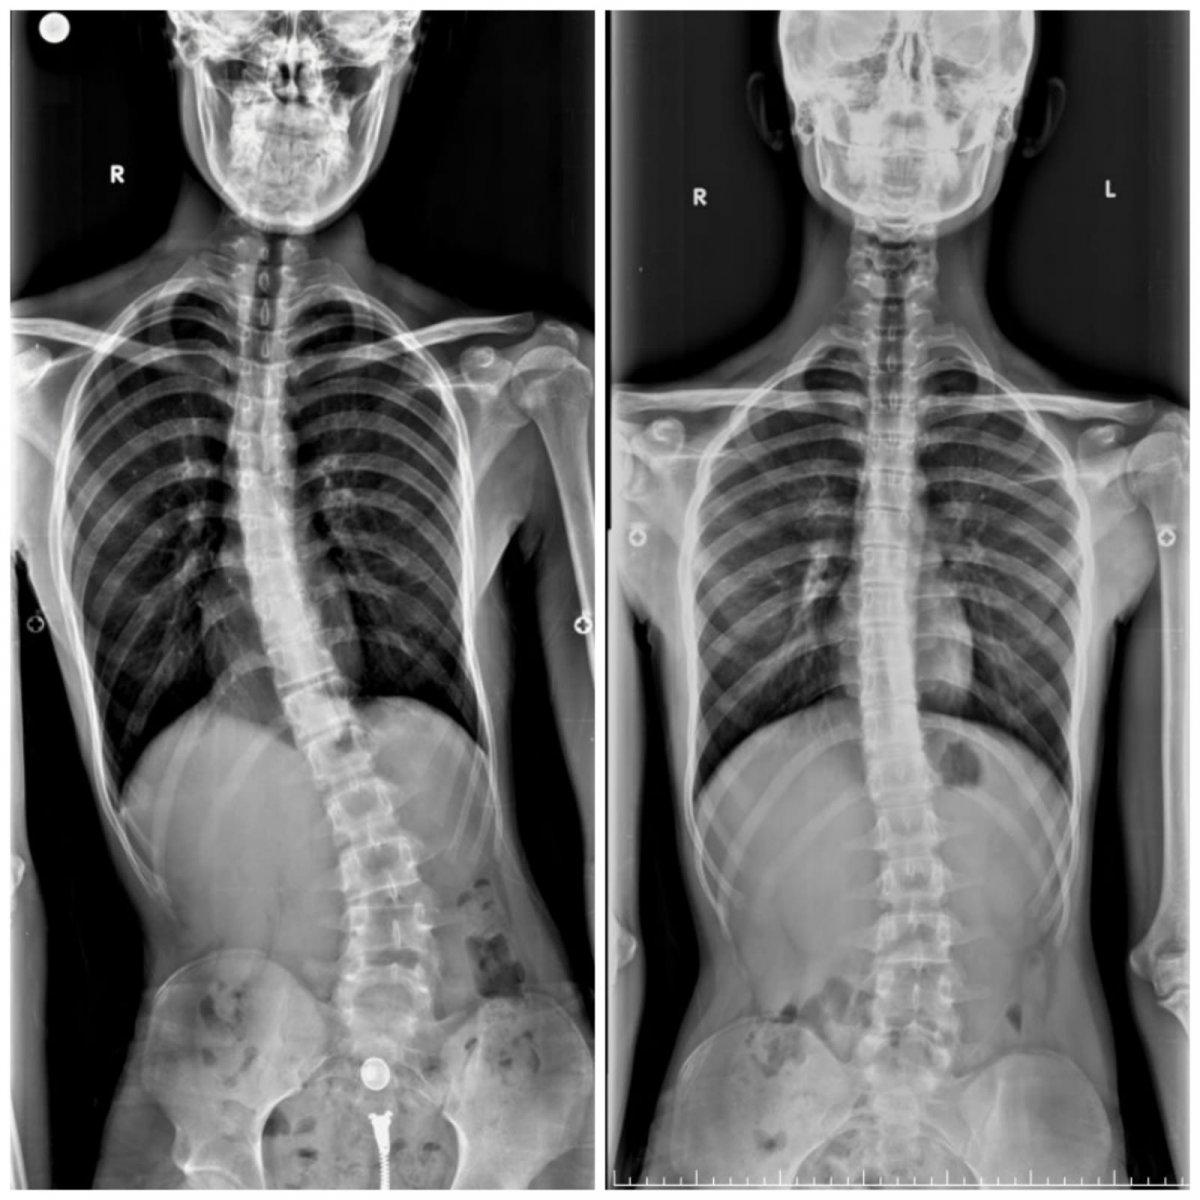

Tüm tetkikleri yeniden yapılan 16 yaşındaki Aziz Koray Diş’e Osteoid Osteoma ismi verilen kemiğin iyi huylu tümörü teşhisi konuldu.

İlk tetkiklerin ardından 25 gün boyunca hastanede kalan Diş, 22’nci gün Doç. Dr. Alauddin Kochai ve ekibi tarafından ameliyata alındı.

Omuriliğindeki tümörün alınması için yapılan operasyon sonrası 2 günde ayağa kalkan Aziz Koray Diş, ameliyattan yaklaşık 2 ay sonra tamamen sağlığına kavuştu.

Aziz Koray Diş’in sosyal hayatını da etkileyecek dereceye gelen eğriliğinin tespiti sonrasında hızlıca tedavi sürecine geçildiğini belirten Sakarya Eğitim ve Araştırma Hastanesi Ortopedi ve Travmatoloji Bölümü'nde görevli Doç. Dr. Alauddin Kochai, şu ifadeleri kullandı:

“Aziz’in bize geldiğinde ciddi bir eğriliği vardı ve bu eğriliğin kaynağı bir türlü bulunamamıştı. Burada gerekli tetkikleri yaparak bu eğriliğin iyi huylu tümör olduğunu belirledik ve buna yönelik yaptığımız cerrahi sonrasında sağlığına kavuştu ve 2 ay içerisinde tamamen sağlığına kavuştu.”